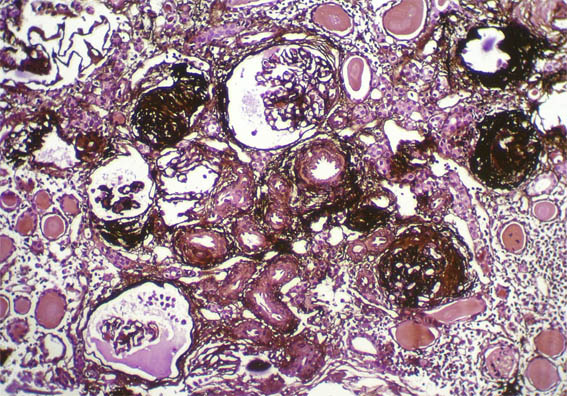

Figura 1.

H&E, X100.